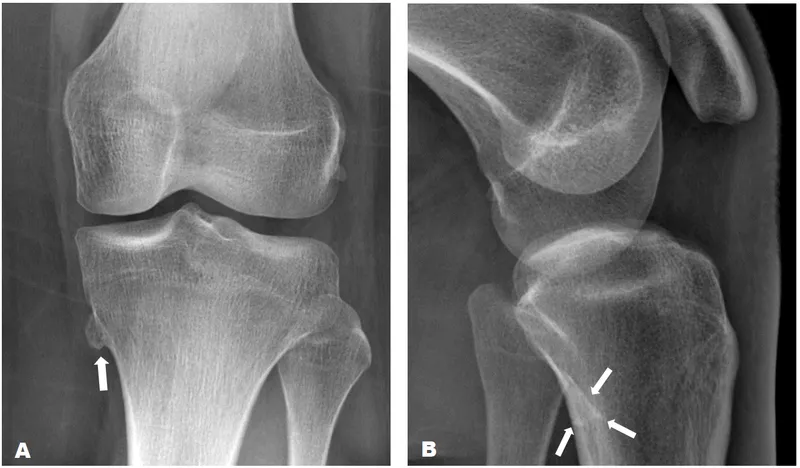

Osteochondroma (Exostosis):

- Most common benign. Age: < 20 yrs.

- Site: Metaphysis (e.g., knee). Cartilage-capped bony spur.

- Radiology: Points away from joint.